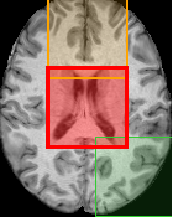

Patch-based Predictions When we use a single patch as input, the results are highly dependent on the area of the brain where the patch is extracted from. We train 27 ResNets for 27 patches, achieving a MAE from around 2.5 to 4.2 years. The patches with the best performance are the ones that include the ventricles or the hippocampus, with MAEs of less than 2.5 and 2.7 years, respectively, and score of 0.80 and 0.76, respectively, as well as patches that include parts of these regions. On the contrary, patches that contain substantial amounts of background perform much worse with a MAE of 3.5-4.2 years and an score of 0.15-0.6. In Figure 3, various patches, colored based on the performance of the corresponding models, are illustrated as part of a whole brain slice.

Based on the results, we conclude that the patches that include parts of the ventricles and the hippocampus tend to predict the age of the subject more accurately with a MAE of less than 3 years, thus our results are consistent with the existing literature [30]. The MAE in some of these cases is lower than that for the baseline network which utilizes the volume of the whole brain, proving that not all parts of the brain are needed for an accurate prediction. Therefore, less computational effort is required for comparable results. On the other hand, patches that include part of the background do not perform as accurately. We observe that although the brain shrinks while age increases, the networks do not manage to capture the changes in the cerebral cortex as accurately. An explanation for this could be the way the images are registered, which reduces size differences between brains, or the relatively small range of existing ages in the dataset, especially of ages beyond 65 years when atrophy tends to accelerate [8]. Furthermore, the use of patches provides a visualization of the parts of the brain that are valuable for age prediction, leading to a more understandable prediction. Although the patches are big and do not provide detailed localization, this work is the first step towards an interpretable and localized brain age estimation. As our next step, we will use smaller patches (e.g. sized 32x32x32 or 16x16x16), either from the whole brain or from the best-performing patches. More localised detection of a deviation from normal trajectories may also be useful for the automatic detection of more focal pathologies such as ventricular enlargement in hydrocephalus or hippocampal atrophy in temporal lobe epilepsies [17].